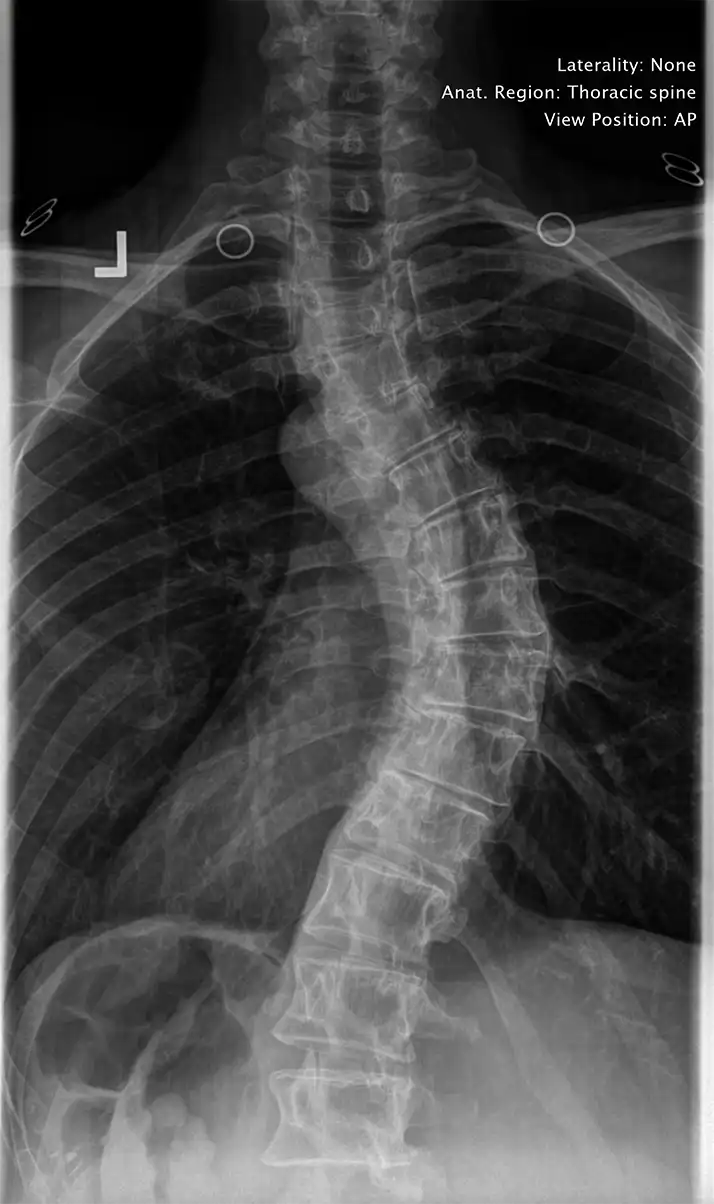

Scoliosis describes abnormal curves of the spine greater than ten degrees. These abnormal curves are laterally displaced, and symptomatic of a greater systemic disease. Scoliosis affects most of the major systems of the body: nervous, digestive, musculoskeletal, endocrine, immune, and can cause severe respiratory and cardiovascular problems. This is due to altered function of the spine, causing interference to the spinal cord and exiting spinal nerves. Poor posture, such as slumped shoulders, a high shoulder, or a high hip can indicate scoliosis or curvature of the spine. Thankfully, if the initial curvature is cared for proactively, the chiropractors in Austin TX are able to keep it from developing scoliosis.

Although there are different kinds of scoliosis, idiopathic (unknown cause) scoliosis accounts for approximately 80 – 85% of cases. Many cases of scoliosis start with a short leg, even as little as ¼ to ½ inch, which then causes the pelvis to drop down, and the spine to curve in compensation. About 1 out of 5 people have a significant short leg. The only way to find out for sure if you have a short leg is to take a specific standing X-ray of the spine and pelvis. You cannot determine a short leg by measuring a person’s leg length with a tape measure. There are too many variables.